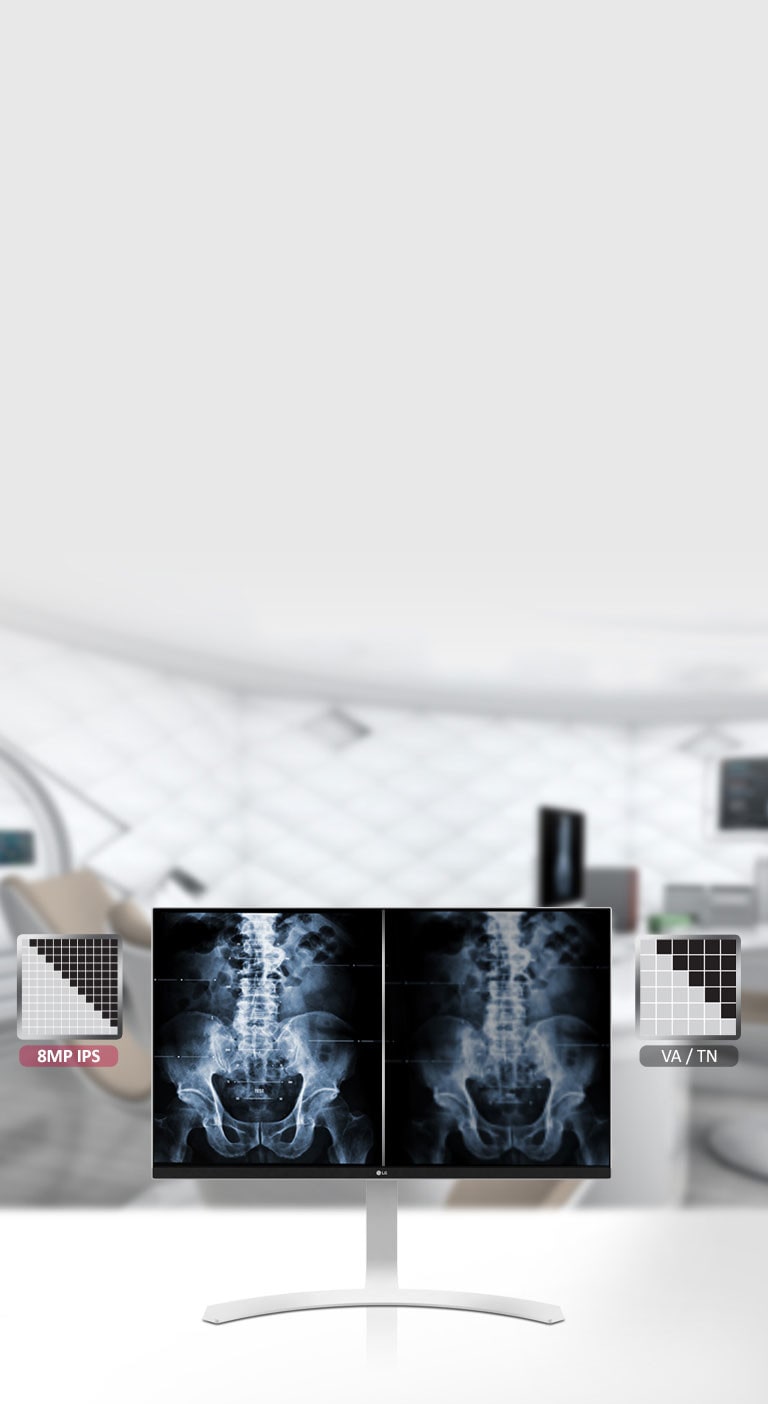

27" (68 cm) | Écran IPS | Résolution UHD 3840 x 2160

27" (68 cm) | Écran IPS | Résolution UHD 3840 x 2160

Conforme DICOM

OUI